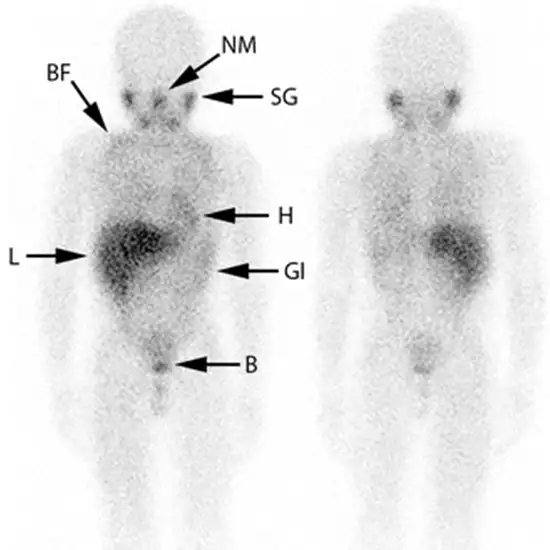

A MIBG scan is a type of nuclear imaging test that can help doctors diagnose and assess certain types of tumours. Nuclear imaging tests use a small amount of radioactive material that is absorbed by your body's tissue.

The tracer is injected into a vein in your arm or hand by a healthcare provider. It takes about 24 hours for the tracer to circulate throughout your body. You'll return the following day for your first scan.